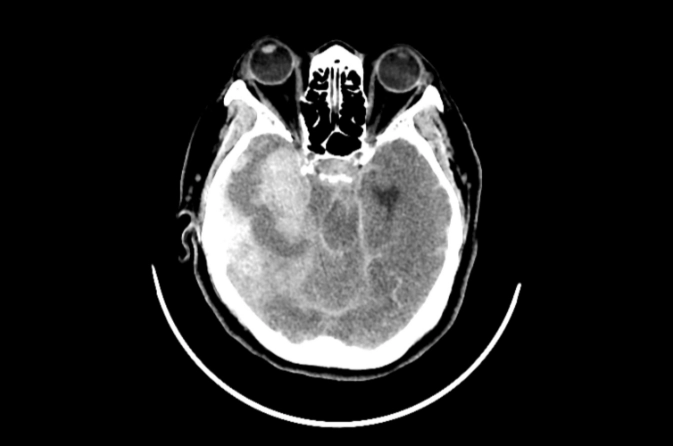

Epidural Hematoma Surgery is performed to remove blood pooled between the skull and the outer layer of the brain, known as the dura mater. This condition usually occurs due to trauma, accidents, or skull fractures and leads to rapid pressure buildup. The surgery prevents brain damage, restores blood flow, and stabilizes the patient. Early intervention is critical for successful recovery.